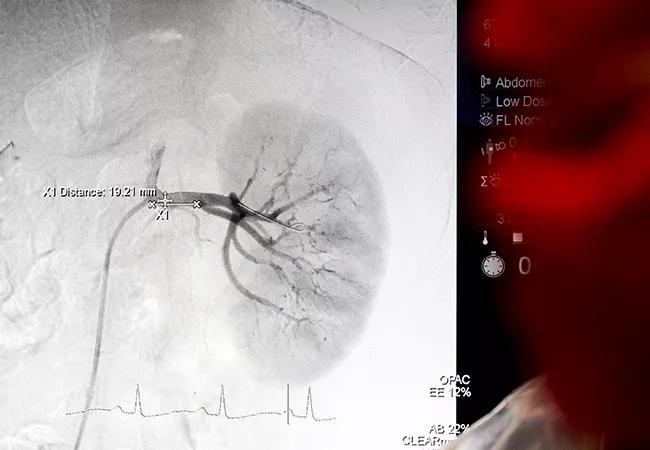

Renal denervation requires inserting a catheter in the femoral artery and taking a renal angiogram to visualize the renal arteries. A balloon catheter is then inserted in the arteries and ultrasound (Paradise) or radiofrequency energy (Symplicity) is delivered through the entire renal arterial system.

“You have to ablate all the nerves,” Dr. Nanjundappa notes. “They usually start at the proximal portion of the artery and go all the way to the kidney parenchyma.”